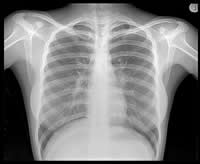

The x-ray works by exposing the body or body part to the radiation. Depending on the density and composition of the tissues and bones, the radiation is absorbed by the object. The rays that do pass through are then captured by a detector or a film that provides a 2-dimensional representation of the structure. The workings of x-rays include how light photons work with atoms and electrons. Visible light photons and x-ray photons are produced by the movement of electrons in different energy levels or orbitals, when they drop to a lower level they need to release energy, and when raise to a higher level they need to absorb energy. The atoms that make up the human skin tissue absorb the energy exerted by light photons. X-ray waves have too much energy and because of the excess energy, they are able to pass through a majority of things. The tissues that makes up the skin has smaller atoms and hence to do not effectively absorb X-ray photons, while the calcium that makes up the bones have larger atoms and can absorb the photons effectively, resulting in the bones showing up white on the negative. The negative that is used to capture images is a transparent plastic film coated with light-sensitive chemicals. When the x-ray waves are propelled at the patient, the waves that pass through skin turns the negative black (this is because of the chemical, which when exposed to light turns dark), while the waves that are absorbed by the body are marked as white on the film.

X-rays became very popular in the medical feild as it allowed the doctors to see past the skin tissues and determine if there are any damages to the bone of the patient. This technique helps them determine if any bones are broken, sprained or may have sustained any other damage without having to open up the patient. Additional advancement to this technology has allowed doctors to even generate 3D images of the object that is scanned giving them a full circular view of the object. X-rays are often good for short use as prolonged exposure to radiation is hazardous to living organisms. X-ray machines are also used at airport terminals and other places that require high amount of security to scan bags, boxes, etc. without having to manually open and search each one of them by hand.